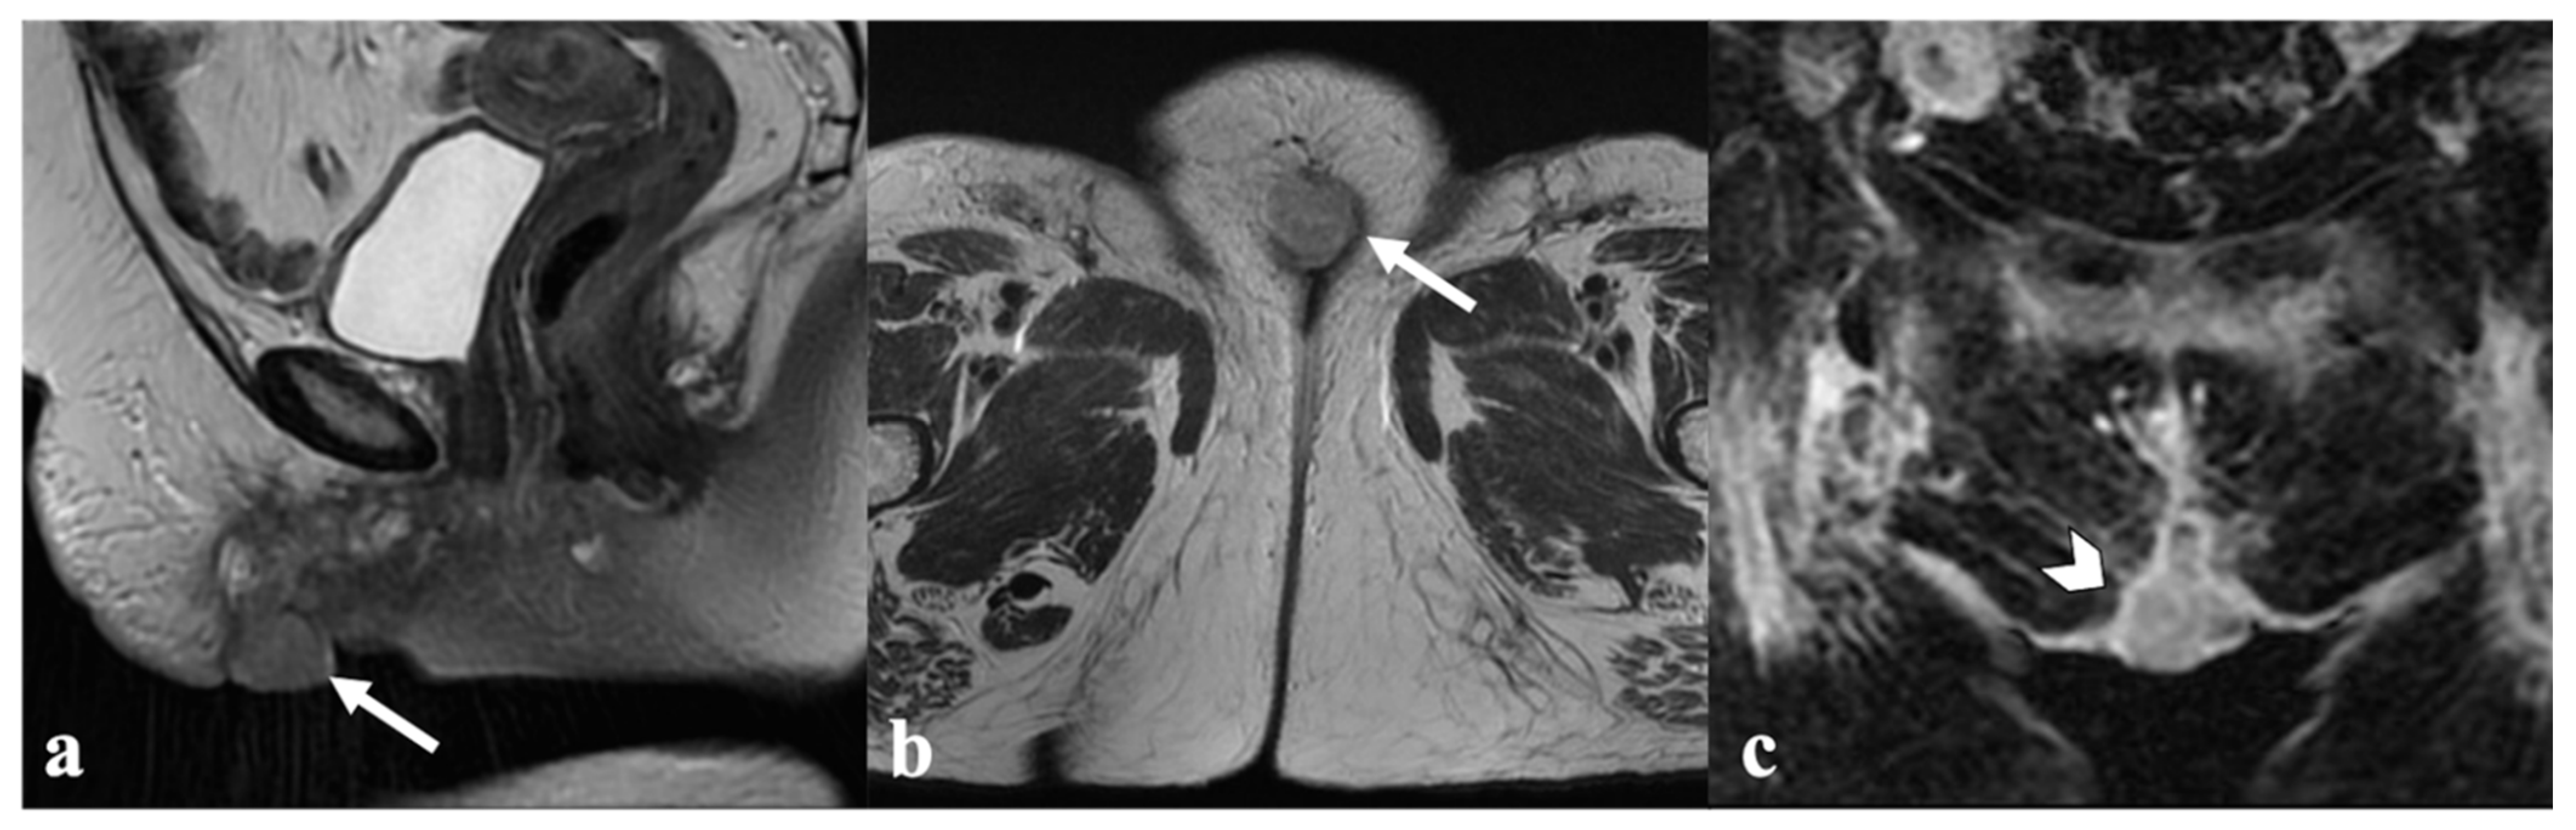

3.4. Bladder and Rectum

4. Post-CRT MRI Findings

4.1. Local Tumor Status and Residual Invasion of Adjacent Organs

5. Vulvar Cancer Recurrence